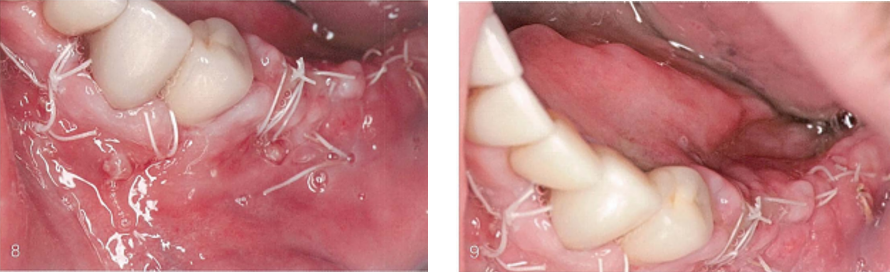

(8)和(9)唇侧观,愈合后5天后组织瓣,可见瓣关闭,瓣边缘和颊舌侧组织瓣之间有脓性渗出物(使用本章节所描述处理方式,有20%的移植材料未取出而留在术区)。